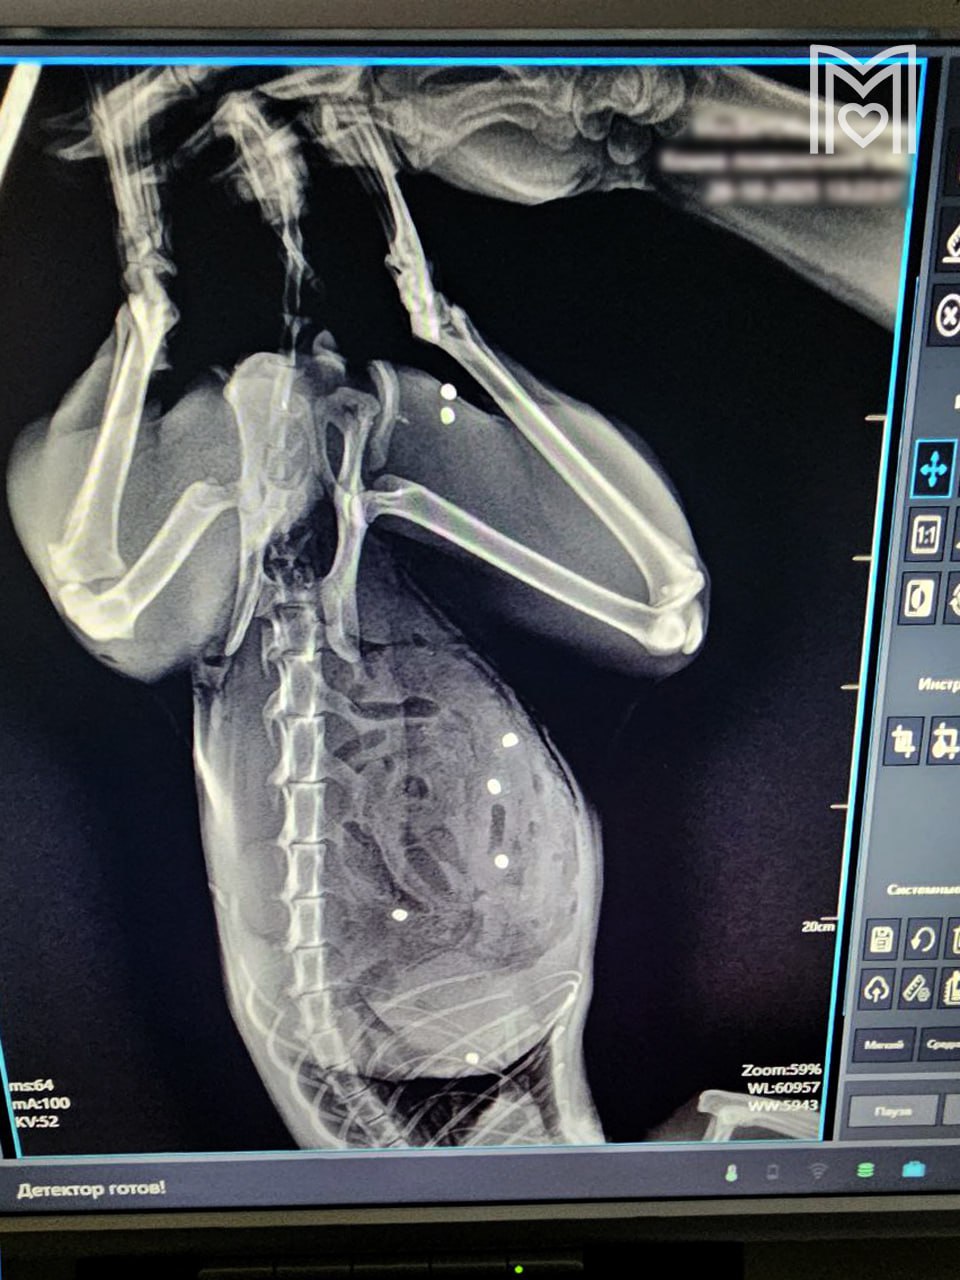

В Зеленограде спасли кота с множественными пулевыми ранениями. По словам владельцев, питомец пострадал во время прогулки в частном секторе, его оперировали более трех часов.